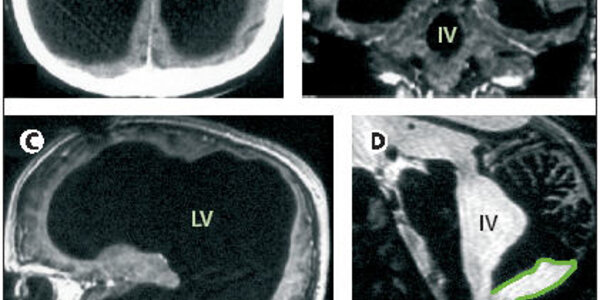

You don't need a big brain, or a high IQ, to have a comfortable life and a good family. Witness the case of this French civil servant, written about by Dr. Lionel Fuillet in The Lancet. At age six months he was treated for hydrocephalus (water on the brain) with a shunt in his head to drain away the fluid. At age 14 he complained of unsteadiness and left leg weakness, which cleared up after the shunt was adjusted. Beyond that his neurological development and medical history were normal. At age 44 the leg weakness returned and he was treated by Dr. Feuillet and colleagues of the Hôpital de…